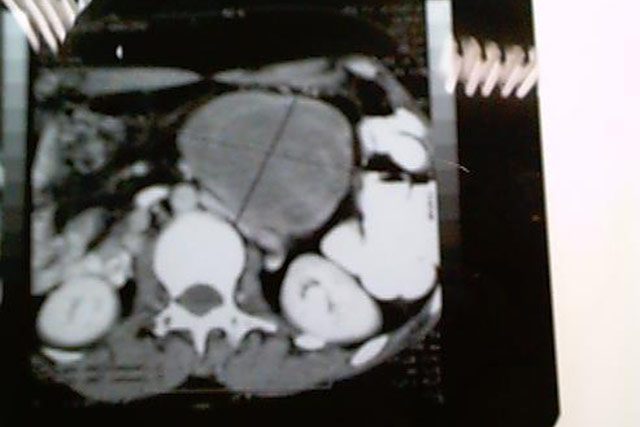

Fibrosarcoma de Mesentério